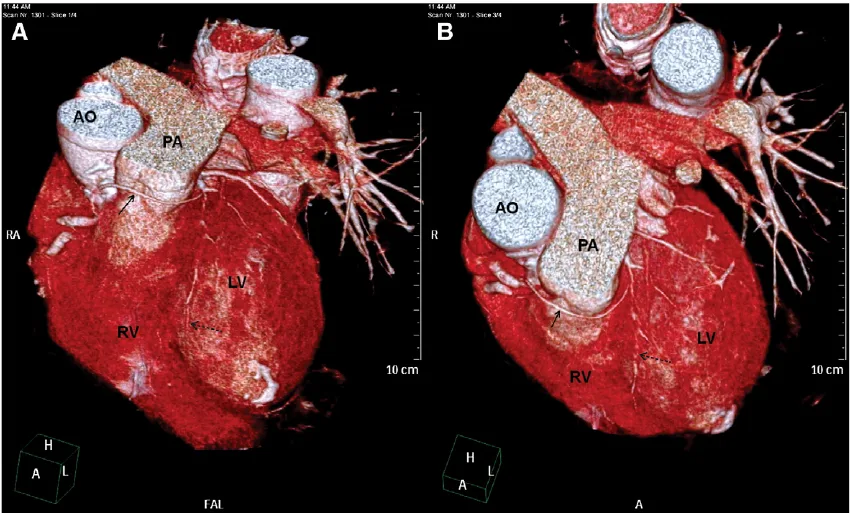

3D CT Scan with VRT Imaging in Navi Mumbai | Henotic Diagnostics

Looking for a 3D CT Scan with VRT Imaging in Kharghar? At Henotic Diagnostics, Kharghar, we provide high-resolution 3D CT scans with Volume Rendering Technique (VRT) for clear visualization of bones, blood vessels, and soft tissues. Moreover, this advanced imaging technique offers precise details, which helps in diagnosing fractures, tumors, vascular diseases, and supports complex surgical planning. In addition, our multi-slice CT scanner ensures accurate images with minimal radiation. Therefore, patients from Kharghar, Panvel, Belapur, Nerul, Vashi, and Navi Mumbai can rely on us. Book your 3D CT Scan today for superior diagnostic accuracy!